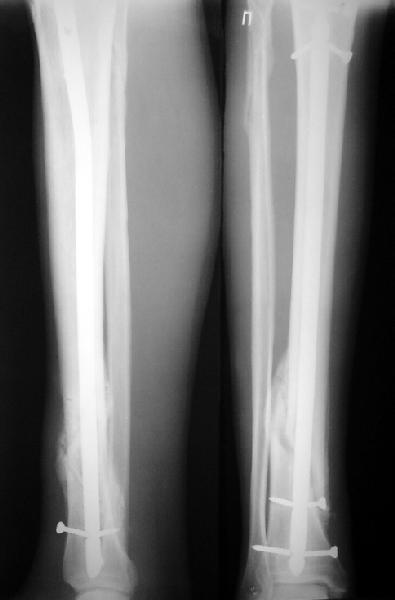

JOM> Кстати, если можно пошлите послеоперационный снимок.

Ok. А также и следующий, в 3 месяца.

Это наглядная демонстрация возможности ранней полной нагрузки при нестабильном по оси повреждении, причем не в самых благоприятных механических условиях - при плохом сопоставлении, со слабым фиксатором.

JOM> Ваш больной имеет счастье, что первым согнулся проксимальный

JOM> замыкающий винт, а не дистальный и гвоздь не пенетрировал

Это не счастье, а тонкий инженерный расчет ;-))

Сверху - один статический винт, а снизу - три. Что раньше сломается? Конечно, он потом и нижние сломал, и Вы правы, если бы верхний динамичесий винт уже уперся бы в нижний край отверстия, будь гвоздь подлинее, перфорировал бы сустав как пить дать.

Как я уже говорил, мы сделали выводы из этого и других подобных случаев. Очевидно, решений проблемы два - либо уменьшить нагрузку, либо увеличить прочность фиксатора. Первое решение работает не со всеми больными, так что пошли по второму пути - мы больше не используем гвозди с запирающими винтами диаметром 4 мм.